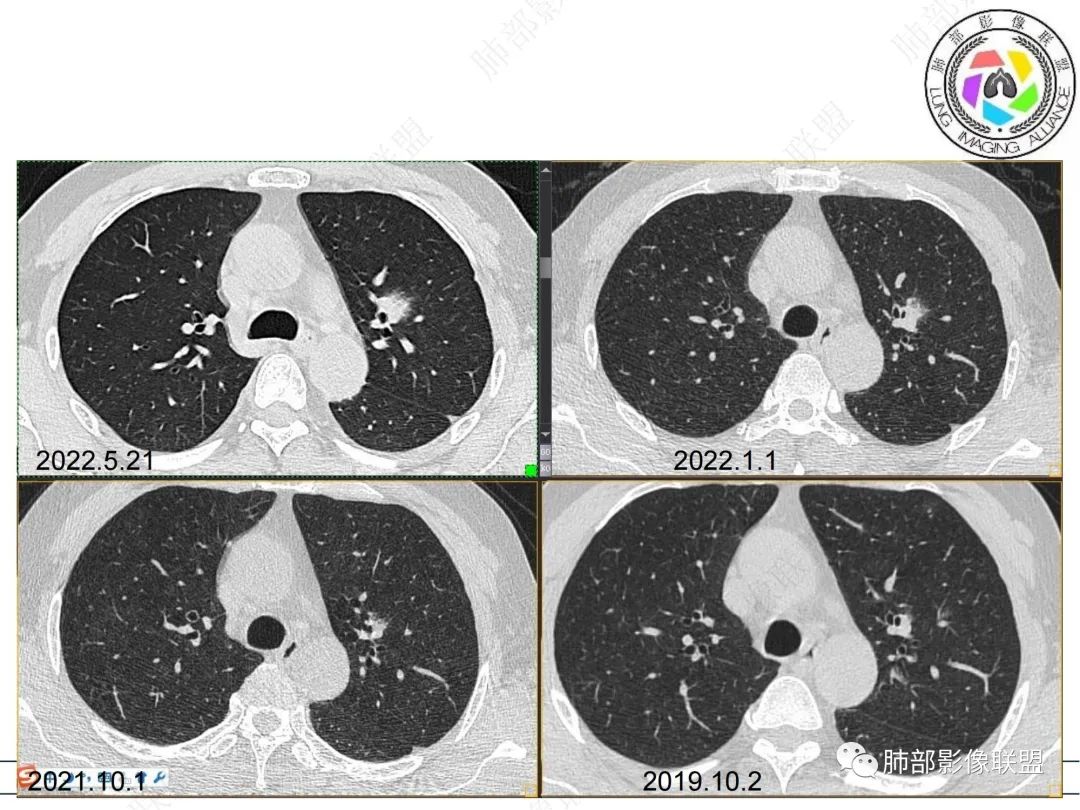

【病例】三年逐渐增大的混合磨玻璃结节,真相是什么?

男性,肺结节3年,发现逐渐增大,影像表现,左肺舌段结节,边缘可见磨玻璃密度影,内部走形下舌段支气管变窄,增强呈持续强化,首先考虑肺腺癌,鉴别炎性肉芽肿,真菌/隐球菌。

中老年男性,左肺上叶中轴区实性结节及周围磨玻璃影,磨玻璃边界似清非清,关键点2019.10-2021.10-2022.05结节持续增大,增强后明显强化。考虑恶性结节可能大,腺癌(黏液腺癌)?鉴别炎性结节。

57岁,属于高危人士;病灶3年逐步增大,肿瘤按理是要考虑的

1、临床:57岁男性,3年逐步增大。孤立病灶持续三年原地坐大,符合肿瘤性病变,恶性程度不高或者早期进展缓慢。良性肿瘤常多年静止或进展极其缓慢。炎性病灶“星火”可以燎原,临床表现也会逐步加重。尽管继发性肺结核可以相对惰性,但病灶强化不明显,多结节、多卫星、多新旧不等,相对清楚硬朗。

2、病灶以实性密度为主,前、外侧蔓延,GGO部分边界清楚,部分欠清

支气管未见受明显侵犯,未见阻塞,壁增厚,狭窄或扩张。